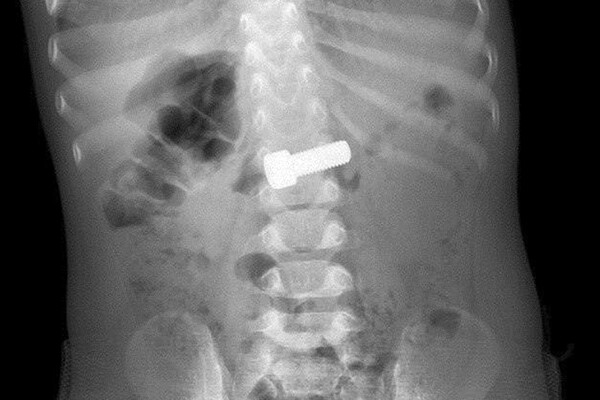

Годовалый ребенок играл и случайно проглотил болт, родители сразу вызвали скорую помощь. В приемном отделении ребенку сделали рентген, который подтвердил нахождение инородного тела в желудке. Врачи-эндоскописты оперативно провели процедуру по извлечению предмета с помощью специальной петли, которая заняла около 15 минут.

По словам медиков, благодаря быстрой реакции родителей, болт не успел причинить серьезного вреда. В противном случае инородное тело могло привести к непроходимости или повреждению стенок желудочно-кишечного тракта. Состояние маленького пациента оценивается как стабильное.